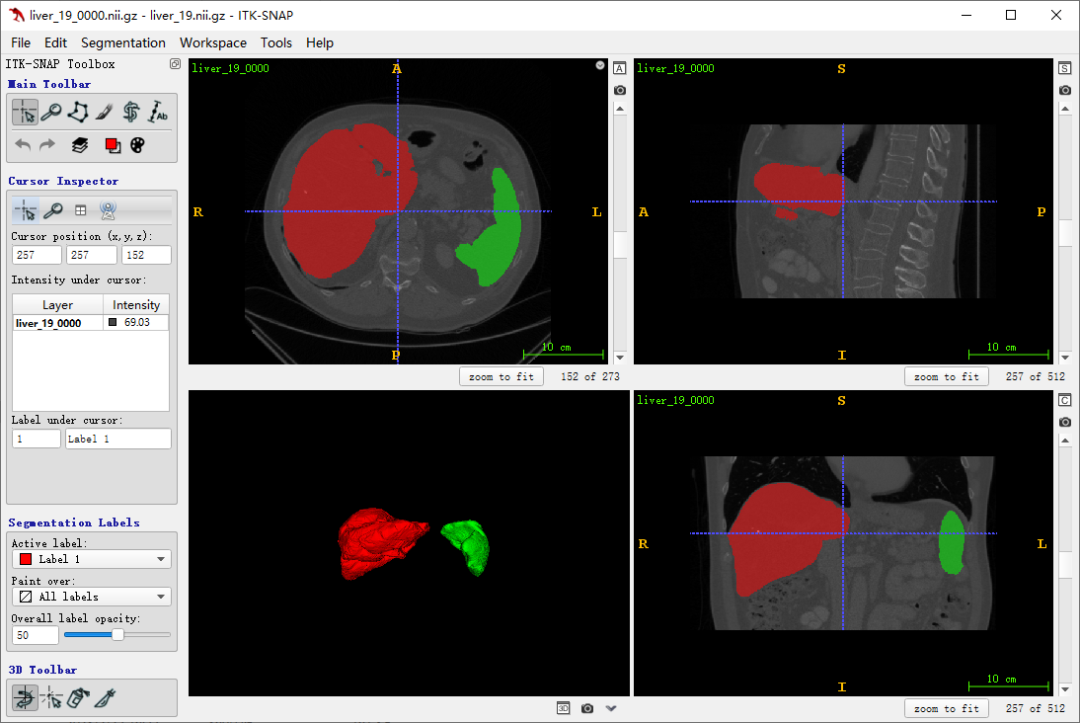

用医疗软件 itk-snap 软件读取原始数据和对应分割标签,展示效果如下图:

分割预测效果

需要把预测结果转换成和原始数据的空间、维度、尺度等参数一致的 Nifit 格式医疗数据文件。对预测的分割结果处理后得到的位置映射到原始数据上才能保证取 ROI 计算CT值时,没有额外的插值。因为肝脏和脾脏都是一个整体连续的器官,因此预测结果转换之前,还需对结果只保留最大连通域,去掉小目标。对88例带标签的数据,经过以上的处理,再重新计算 Dice 。最终反馈肝脏有0.954mDice,脾脏有0.911mDice。